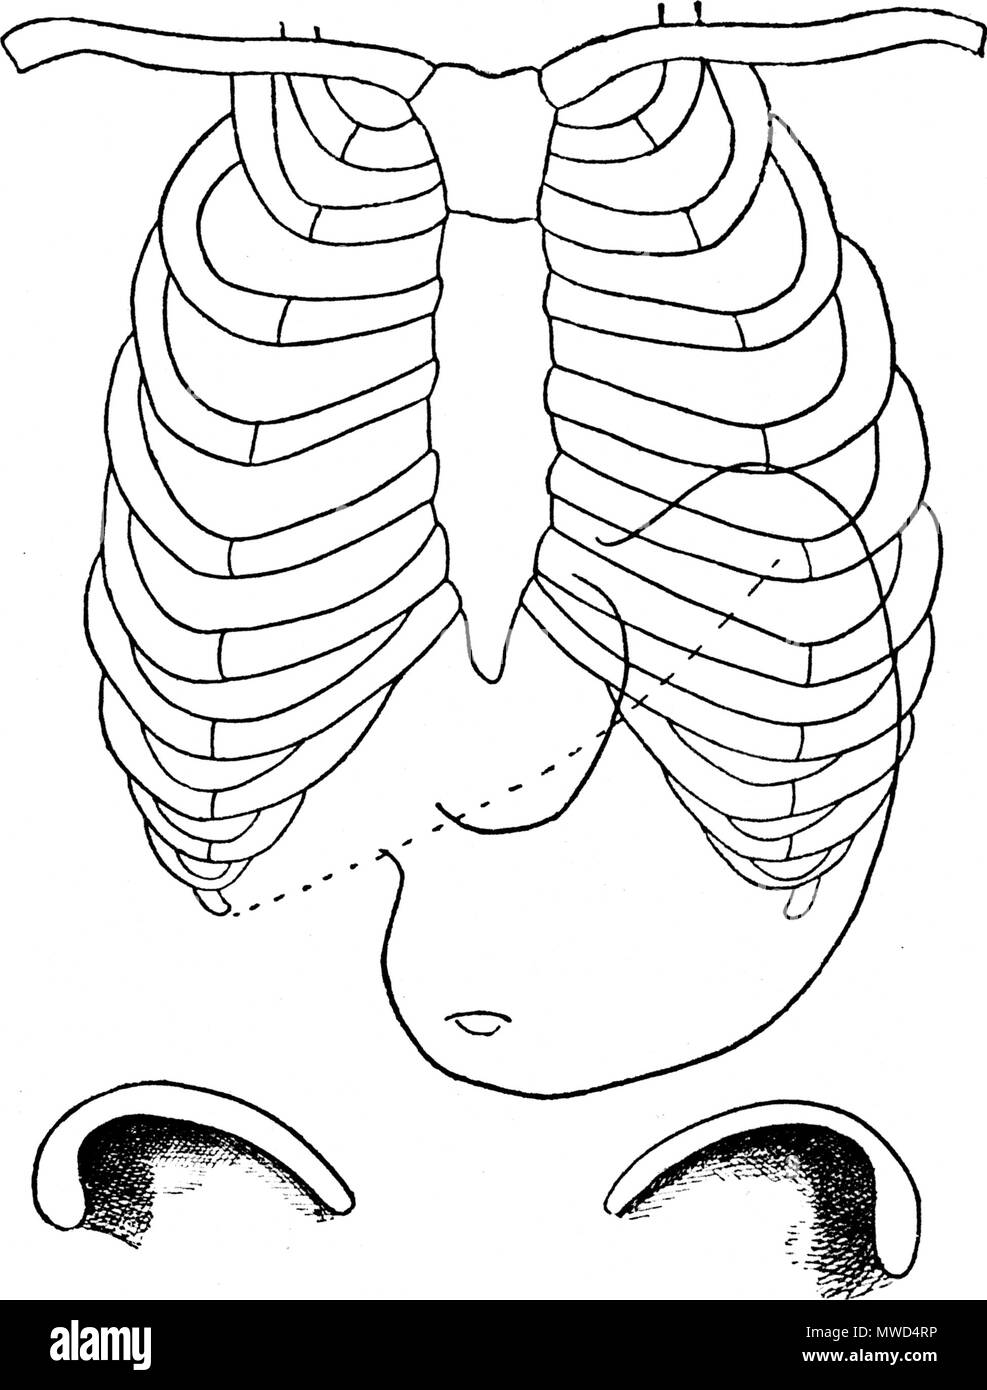

. Français : Figure 1 (d'après Boas); THORAX ET ESTOMAC NORMAUX; - - - - - - Bord inférieur du foie. Diaphragme. G Gros intestin. English: Figure 1 (according to Boas); NORMAL THORAXES AND STOMACH; - - - - - - lower Edge of the liver Diaphragm. G Large intestine . 1892. Le dr Eugène Chapotot 169 EstomacCorset page017 Stock Photohttps://www.alamy.com/image-license-details/?v=1https://www.alamy.com/franais-figure-1-daprs-boas-thorax-et-estomac-normaux-bord-infrieur-du-foie-diaphragme-g-gros-intestin-english-figure-1-according-to-boas-normal-thoraxes-and-stomach-lower-edge-of-the-liver-diaphragm-g-large-intestine-1892-le-dr-eugne-chapotot-169-estomaccorset-page017-image189004859.html

. Français : Figure 1 (d'après Boas); THORAX ET ESTOMAC NORMAUX; - - - - - - Bord inférieur du foie. Diaphragme. G Gros intestin. English: Figure 1 (according to Boas); NORMAL THORAXES AND STOMACH; - - - - - - lower Edge of the liver Diaphragm. G Large intestine . 1892. Le dr Eugène Chapotot 169 EstomacCorset page017 Stock Photohttps://www.alamy.com/image-license-details/?v=1https://www.alamy.com/franais-figure-1-daprs-boas-thorax-et-estomac-normaux-bord-infrieur-du-foie-diaphragme-g-gros-intestin-english-figure-1-according-to-boas-normal-thoraxes-and-stomach-lower-edge-of-the-liver-diaphragm-g-large-intestine-1892-le-dr-eugne-chapotot-169-estomaccorset-page017-image189004859.htmlRMMYDWHF–. Français : Figure 1 (d'après Boas); THORAX ET ESTOMAC NORMAUX; - - - - - - Bord inférieur du foie. Diaphragme. G Gros intestin. English: Figure 1 (according to Boas); NORMAL THORAXES AND STOMACH; - - - - - - lower Edge of the liver Diaphragm. G Large intestine . 1892. Le dr Eugène Chapotot 169 EstomacCorset page017